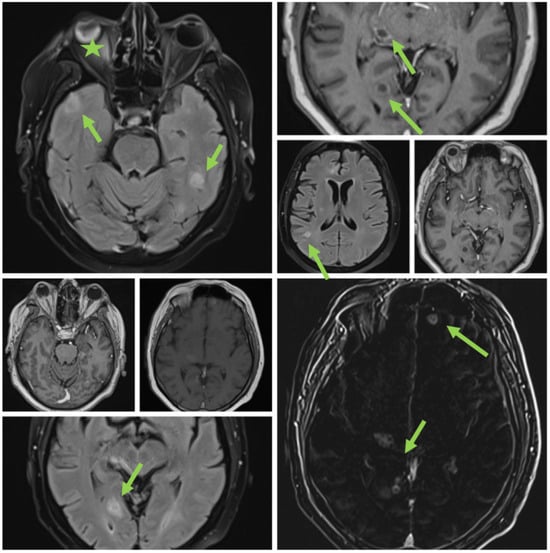

In early May 2023, the patient developed a respiratory illness that was treated with iv gentamycin and ceftriaxone for 7 days in a territorial hospital and was discharged. In late May 2023, he developed right retrorbital pain, with a painful right red eye with acute vision loss, headaches, 7 kg weight loss, and aggravated fatigue that were not controlled with usual medication and cough. The patient was admitted to the Internal Medicine Department for further evaluation. We performed a native cranial CT (Figure 1) and an MRI without contrast which showed multiple lesions—10—that were classified as undetermined lesions on the CT scan and possible abscessed metastases on the MRI.

Figure 1. Initial cranial CT (no contrast).